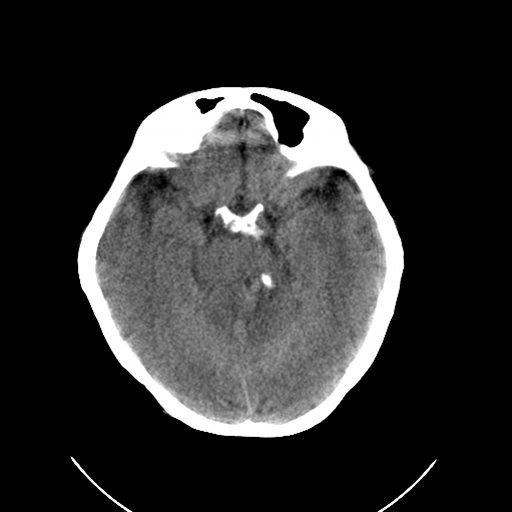

标题: CL0976:颅骨凹陷征 [打印本页]

标题: CL0976:颅骨凹陷征

女,56岁,头痛,没有其他的神经系统的阳性体征

颅底陷入是枕大孔周围骨,包括枕骨基底部、髁部和鳞部上升向颅腔内陷入的畸形。环、枢椎也随之上升、突入。多属枕骨及环枢椎先天性发育异常,也可继发于引起颅底软化的疾病、成骨不全或佝偻病等。

颅底凹陷症!这样横断位未见过,平时都是颈椎侧片所示。建议颈椎mr检查。

颅底凹陷是压迫小脑所以应该有受压的症状,如走路不稳,醉酒状态等.

颅底凹陷.典型.